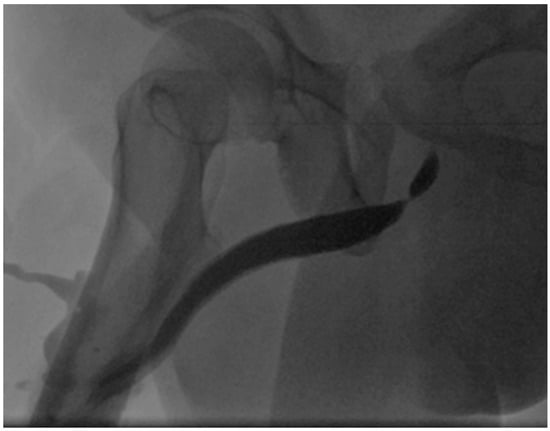

The Presentation and Treatment of Myointimoma: A Systematic Review and the First Case Report of Penile Myointimoma as a Cause of Urethral Obstruction

by Deirdre Maria König-Castillo, Armin Henning, Richard Wasicky, Clemens Kinsky, H. Christoph Klingler and Eva M. Compérat

Background/Objectives: Myointimoma is a rare, benign soft tissue tumor of the penis. We present a systematic review of the current literature and a case report of a 33-year-old male with a urethral stricture without discernible risk factors. Our aim was to investigate current [...] Read more.

Background/Objectives: Myointimoma is a rare, benign soft tissue tumor of the penis. We present a systematic review of the current literature and a case report of a 33-year-old male with a urethral stricture without discernible risk factors. Our aim was to investigate current knowledge on Myointimomas and increase the awareness of this entity. Methods: A systematic literature search was conducted across EMBASE, MEDLINE, PubMed, Scopus, Web of Science, and Google Scholar. Only 30 previously reported cases of this tumor are known—all located at the glans penis or in close proximity to it. Results: After the exclusion of non-eligible studies, 14 studies were included. Conclusions: Myointimomas are a relevant differential diagnosis in recurring cases of bladder outlet obstruction. Full article